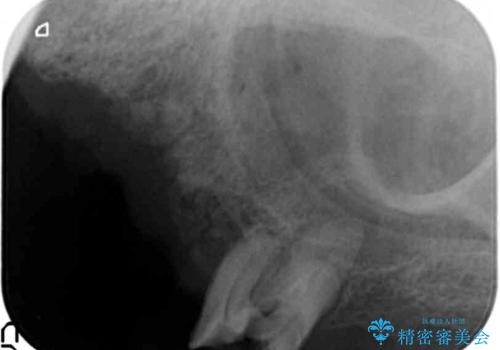

精査したところ、全顎的な重度の歯周病により左上臼歯部は残根(左上6)を残してすべて欠損していました。

禁煙指導と歯周病治療後、左上臼歯部のソケットリフト(上顎洞底挙上術)及びインプラント治療(左上457埋入)を行いました。